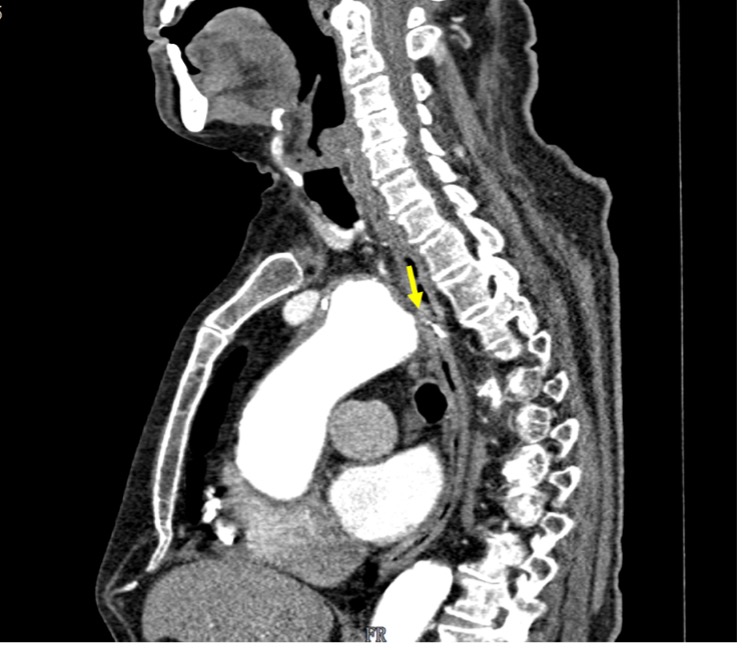

Aortoesophageal fistula: A rare cause of upper gastrointestinal bleeding

A 86-year-old male with hypertension, diabetes and ischemic heart disease, was admitted in the emergency department due to melena with hemodynamic instability. On upper endoscopy no lesions were found. He was admitted in the ICU and next-day reassessment esophagogastroduodenoscopy was normal. On the eighth day of hospitalization, the patient had new-onset hematemesis with hemodynamic instability. Esophagogastroduodenoscopy revealed an esophageal 10mm non-ulcerated mucosal depression with a visible vessel at 20cm from the incisors, closed with 3 hemoclips. Thoracic CT angiography showed a brachiocephalic trunk aneurysm with aortoesophageal fistulization. He was not a candidate for vascular treatment. No rebleeding at 2-month follow-up.